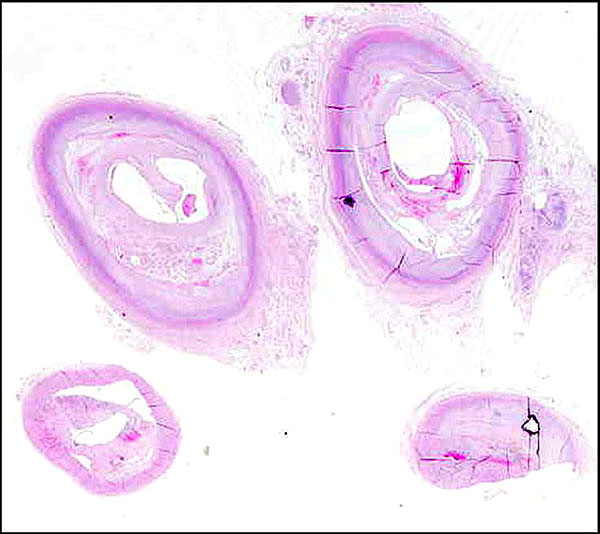

Arteriosclerosis del Polígono de Willis

Placas de ateroma